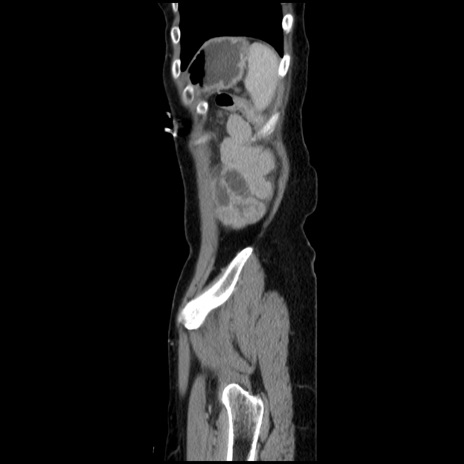

冠状断像